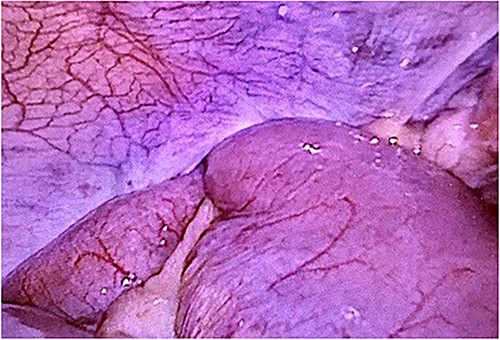

Computed tomography revealed caliber changes in the small bowel at the site of post-hernia repair in the left inguinal region (Figs 1 and 2), and the patient underwent laparoscopic surgery under general anesthesia. Intraperitoneal observation revealed that the peritoneal suture in the left inguinal region was detached, and a hole in the peritoneum had formed a hernial orifice (Fig. 4), causing SBO because of preperitoneal herniation (Fig. 3). The hernia was released, the peritoneal hole was sutured again and the surgery was completed. The postoperative course was good, and the patient was discharged from the hospital on the third postoperative day after reoperation.

The closed peritoneum was lacerated, and the small bowel was incarcerated in the preperitoneal space.